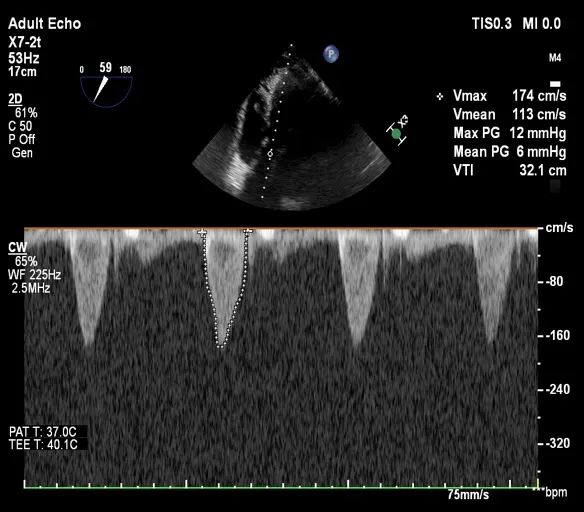

术后即刻评估:

术后平均压差在6mmHg左右,几乎无反流,瓣膜正常工作。